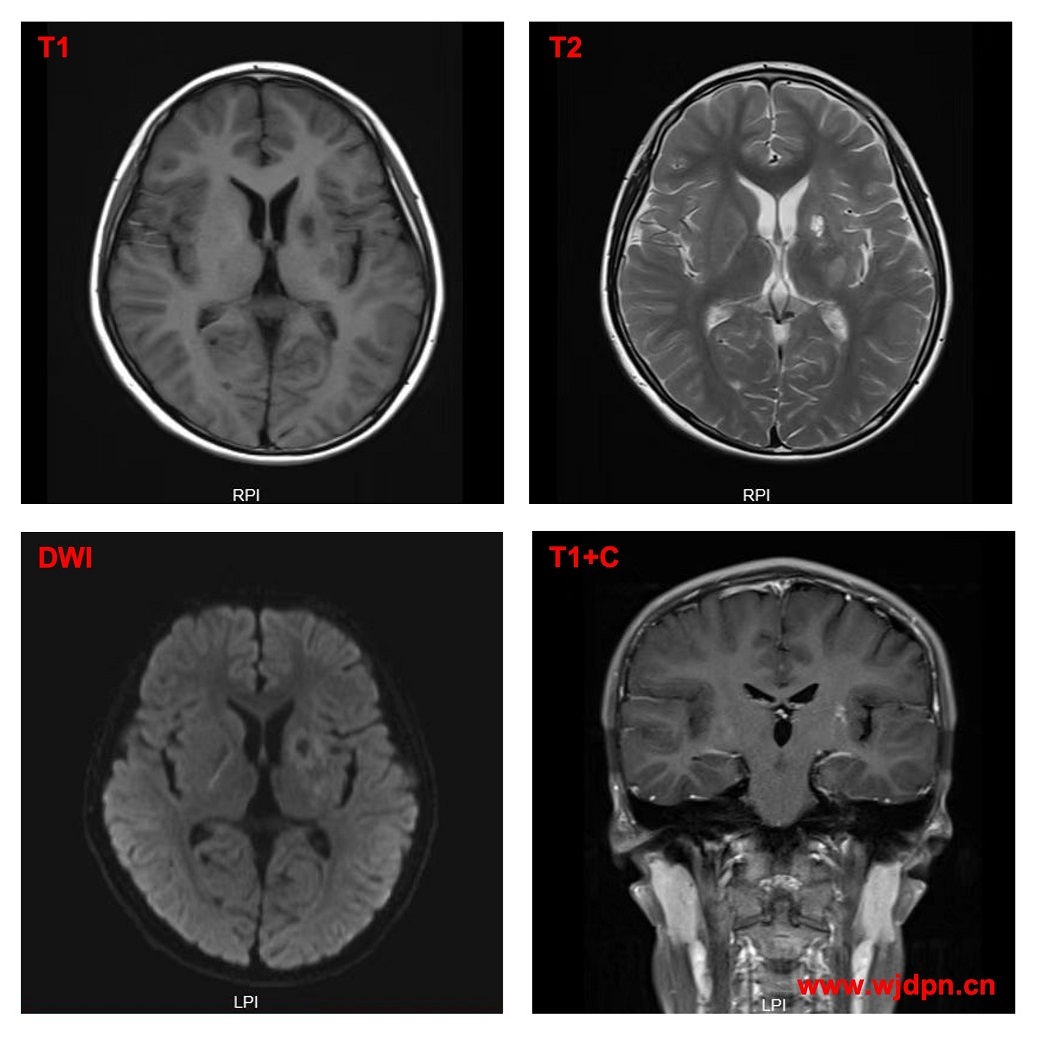

Case 10(a) Right basal ganglionic mixed germ cell tumor. (b) 1 month

From wjdpn.cn

中枢神经系统生殖细胞肿瘤MRI表现 儿童癫痫长程管理 Basal Ganglia Germ Cell Tumor primary cns germ cell tumours can, very rarely, develop at other anatomical sites, including the basal ganglia, thalamus, cerebellum, and spinal cord. We recommend that patients with such primary lesions are assessed by an experienced multidisciplinary team, but the specific details and descriptions of response assessment at these sites is. due to the rarity of basal ganglia germ. Basal Ganglia Germ Cell Tumor.